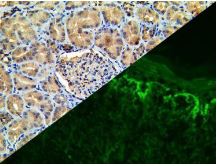

Bio SB has developed a highly sensitive Immunofluorescence and non-biotin monovalent Fab micropolymer IHC detection systems for the detection of IVD antibodies for Complement (C1q, C3c, C3d, C4c, C4d), Serum Proteins (Albumin and Fibrinogen) and Immunoglobulins (IgA, IgD, IgE, IgG, IgM, Kappa and Lambda) related to autoimmune conditions. Our innovative IF and IHC detection systems and high affinity antibodies, have opened the doors for a faster and accurate Immunofluorescence and Immunohistochemistry applicable to Autoimmune Disease like Nephropathies and Lupus.

These antibodies and detection systems are intended for use in Immunohistochemical (IHC) and Immunofluorescence (IF) applications of formalin-fixed paraffin-embedded tissues (FFPE), frozen tissue sections and cell preparations.

Rabbit FluoroDetector FITC |

Rabbit FluoroDetector FITC with FluoroMounter |

Rabbit FluoroDetector FITC with FluoroMounter with DAPI |